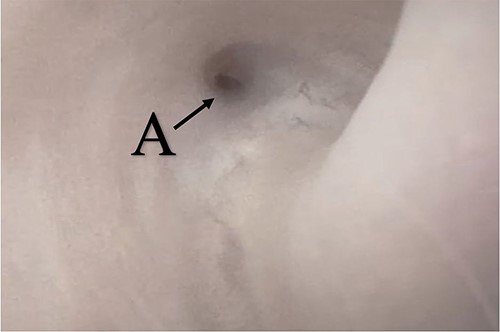

A 38-year-old male was referred to our tertiary hospital due to recurrent urethral stricture for further evaluation and management. His history revealed multiple failed attempts of DVIU, anastomotic urethroplasty and urethroplasty with pedicled fasciocutaneous flap in 2019. Nine months after his surgery, he had complete retention due to stricture recurrence and he underwent multiple dilatations and DVIU but his stricture keep recurring. He was referred to us for definitive management. He was on a suprapubic catheter. Initial workup included retrograde, antegrade cystoscopy and urethrogram. First, an antegrade cystoscope was introduced. The bladder neck, internal sphincter and verumontanum were identified. However, there was no external sphincter due to damage from the previous procedures. A pinpoint opening in the dorsal area of the urethra was seen about 1-cm distal to the verumontanum (Fig. 1, lumen A). Also, a blind-ended urethra in the ventral area was identified (Fig. 2, lumen B). It is most likely from the previous flap. Additionally, the retrograde urethrogram showed that the contrast was only going from the pinpoint hole in the dorsal side of the urethra Fig. 3. Retrograde cystoscopy also showed a blind-ended in the proximal bulbar urethra. We could not identify the small hole that we saw from the antegrade cystoscopy. After initial workup, he was counseled in the clinic for dorsal only buccal mucosal graft (BMG) urethroplasty for which he agreed.

(lumen B): A blind-ended urethra in the ventral area of the urethra as pointed in the arrow.